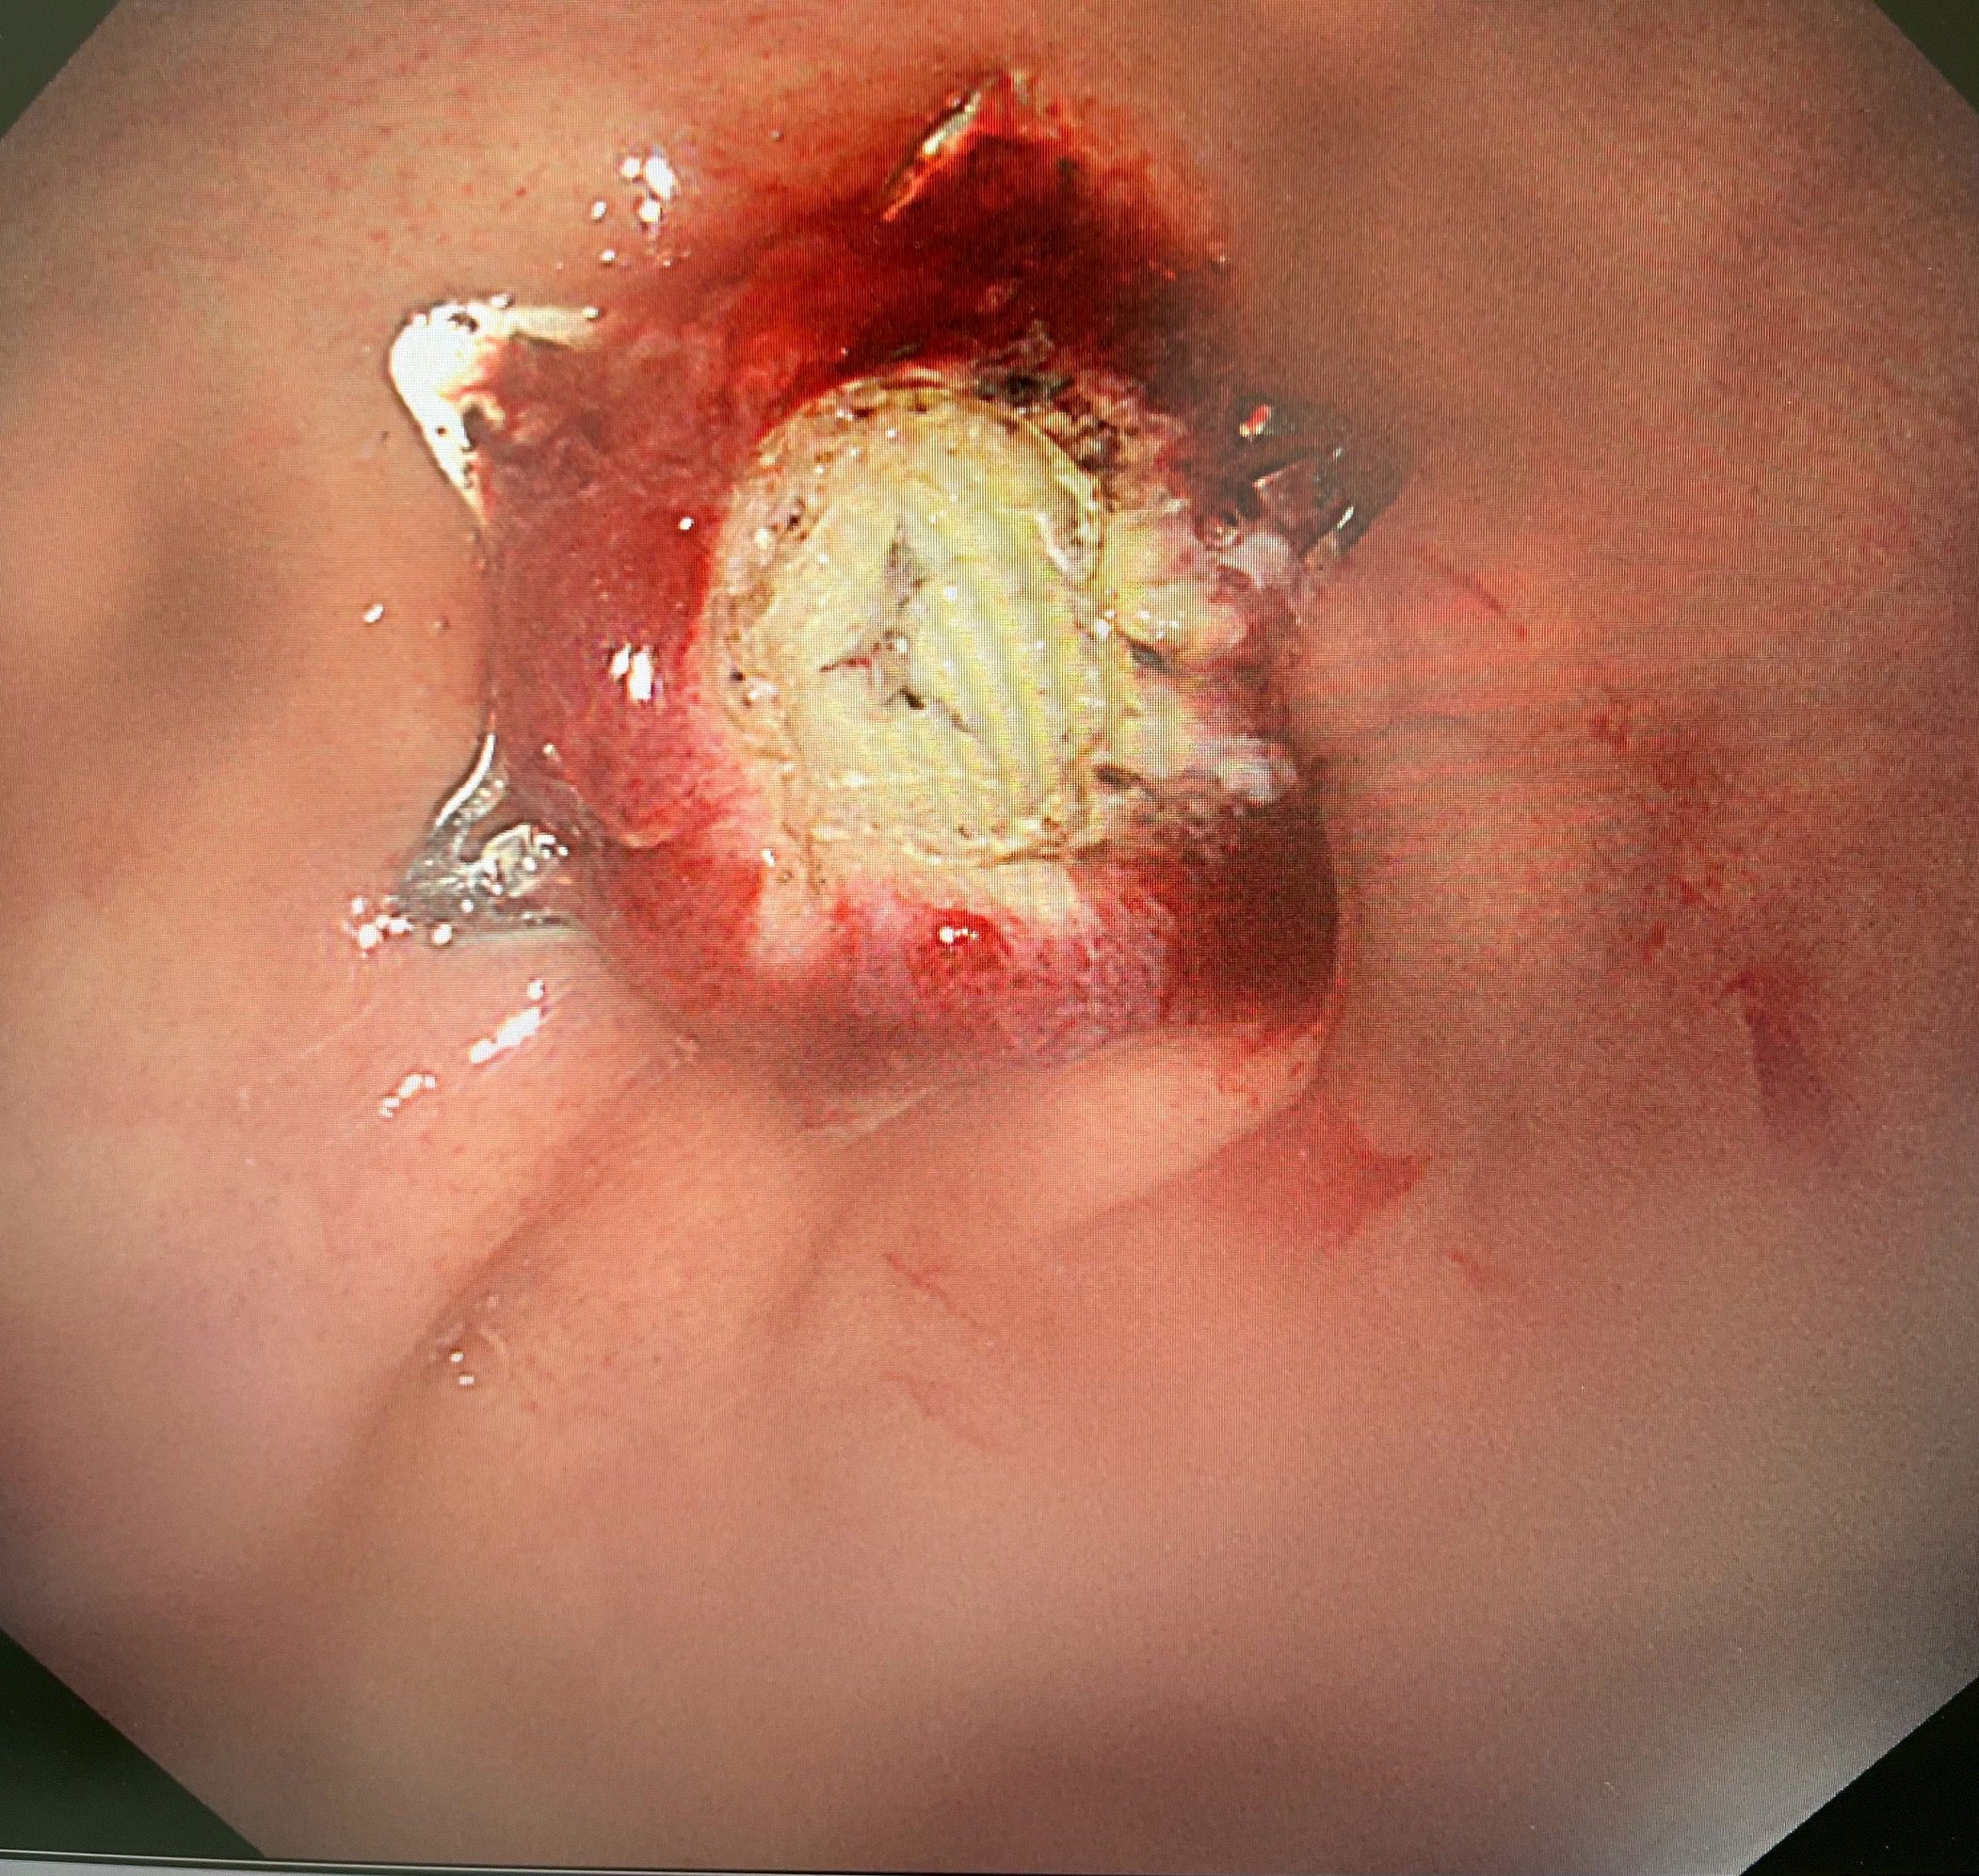

IMG 0041

「手術過程非常順利」,陳鴻運醫師描述:「我們透過內視鏡直視下將腫瘤完整切除,並立即使用pad lock clip閉合裝置關閉胃壁缺損。患者麻醉醒後完全沒有任何不適,沒有腹痛、腹脹等症狀。」

快速康復:術後12小時進食、第二天出院

最令人驚喜的是患者的恢復情況。傳統手術後患者通常需要禁食數天,等待腸胃功能恢復,而這項新技術讓患者在術後12小時就開始進食流質食物,第二天已能進食軟質食物且無任何不適,隨即出院返家。